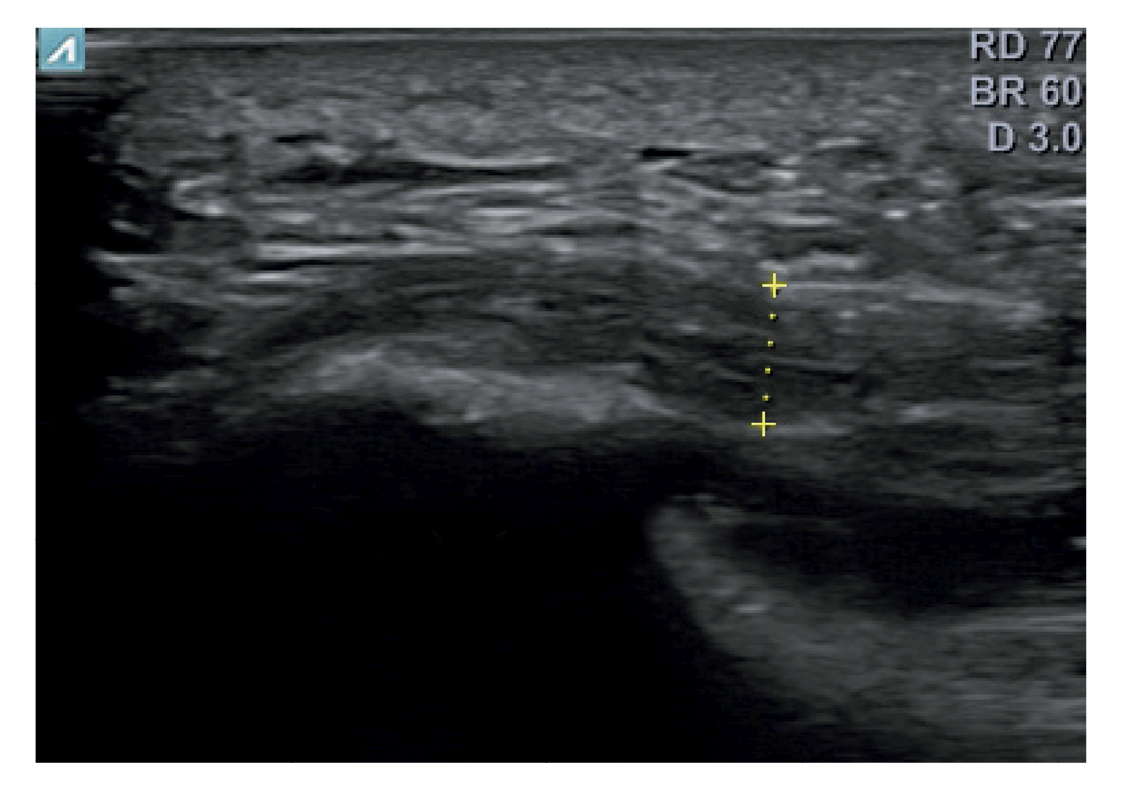

El diagnóstico se estableció en base a los síntomas y se confirmó mediante ecografía con equipo de alta resolución (Alpinion Ecube 9, ALPINION MEDICAL SYSTEMS Co., Ltd., República de Korea) con transductor lineal de 6 a 12 MHz (Figuras 2 y 3).

Figura 2. Investigador con la sonda lineal para la medición del grosor de la fascia plantar.

Figura 3. Área de medición del grosor de la fascia plantar. La línea punteada corresponde con la medición del grosor.